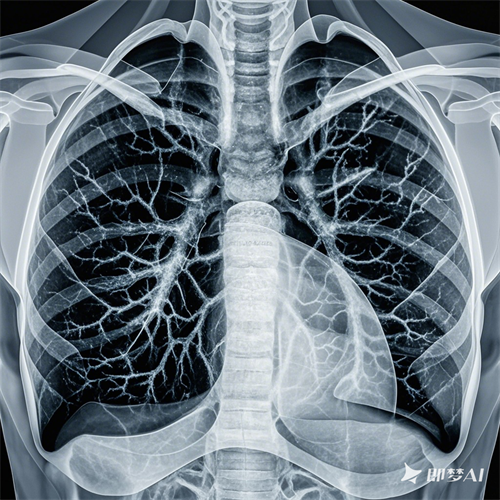

现代医学将肺结节定义为肺部直径小于3厘米的圆形或椭圆形病变。这些结节可能是由炎症、感染、结核等良性原因引起的,也可能是肺癌的早期迹象。因此,关键在于判断结节的良恶性。中医则认为肺结节的形成与气血运行不畅、痰湿凝聚等内在因素密切相关。

1. 及时就医:一旦发现肺结节,应立即就医进行详细检查,以确定结节的性质。现代医学的影像学检查是评估结节良恶性的关键工具。